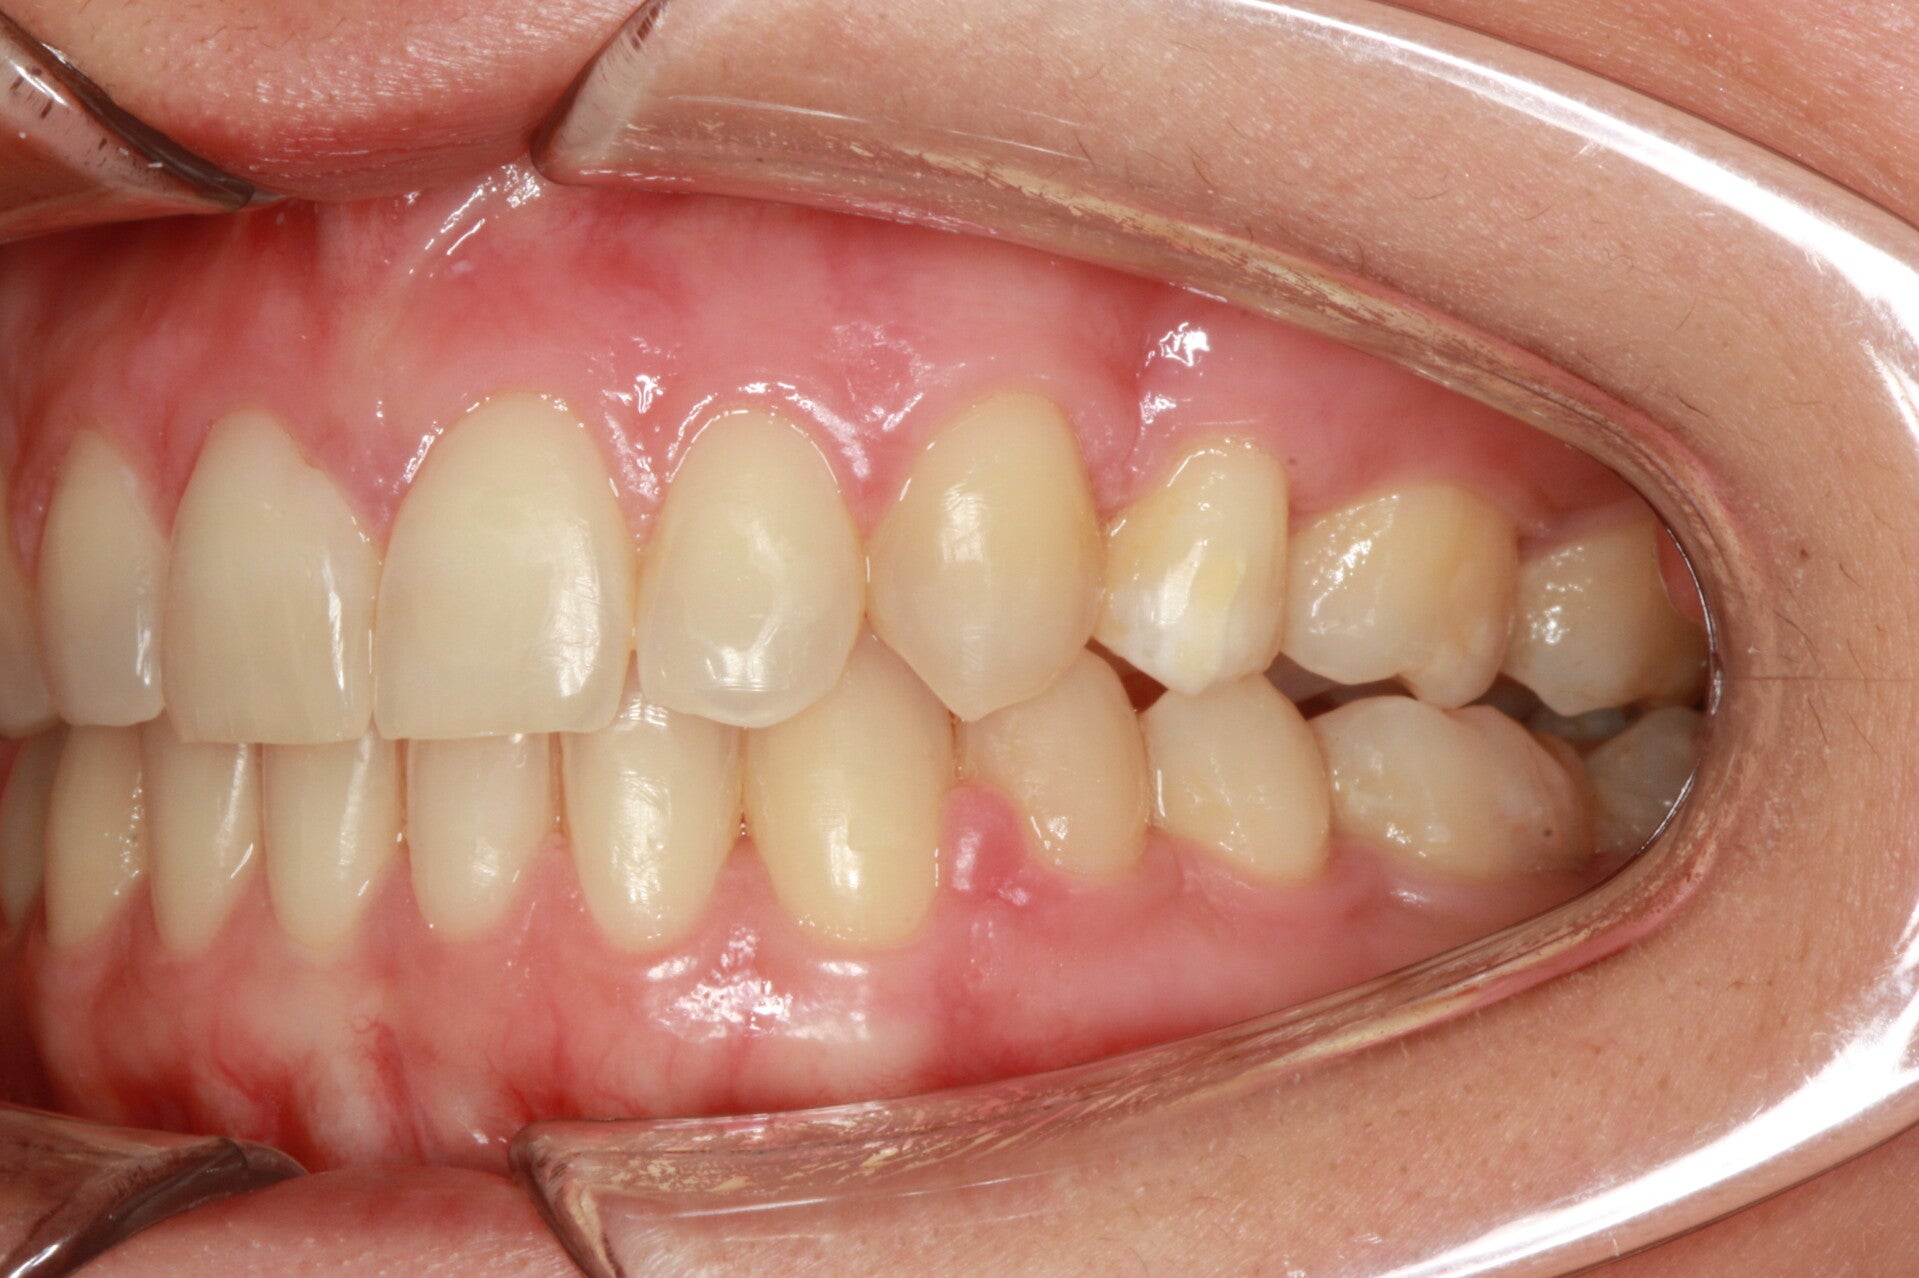

Questo mese vi presentiamo G.G. f. di15aa. Ha una seconda classe suddivisione destra molare e canina. richiesta Allineamento.

FOTO INIZIALI PRE TRATTAMENTO ORTODONTICO